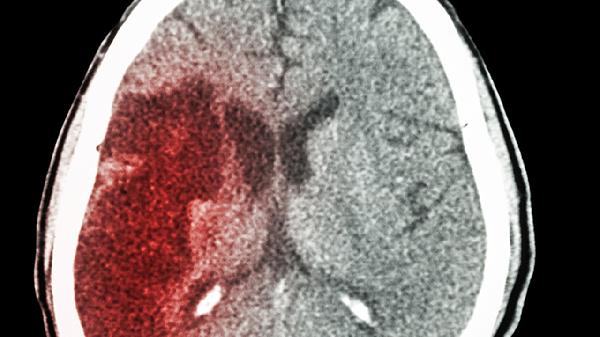

脑出血患者通常表现为突发剧烈头痛、呕吐、意识障碍或肢体偏瘫,症状与出血部位和出血量密切相关。典型体征包括血压急剧升高、瞳孔不等大、病理反射阳性,严重者可出现脑疝。影像学检查可见脑实质内高密度出血灶,治疗需紧急降颅压,必要时行血肿清除术,常用药物有甘露醇注射液、呋塞米注射液控制脑水肿,氨甲环酸注射液预防再出血。